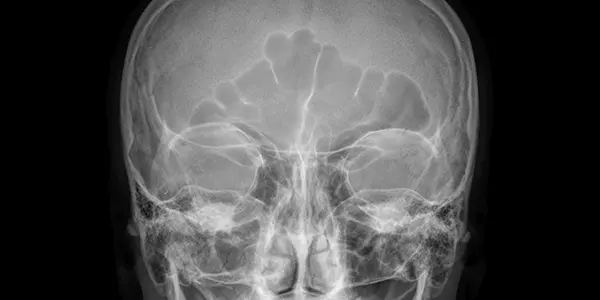

Рентген придаткових пазух носа

Рентгенографія лицевої ділянки черепа і придаткових пазух носа – це найінформативніший спосіб виявлення захворювань і патологічних процесів в порожнинах лицьової частини черепа.

Дослідження просте, швидке. Не вимагає ніякої попередньої підготовки. На знімку лікар-рентгенолог бачить всі пазухи і може легко оцінити картину.

Якщо в пазухах все нормально, то лікар буде бачити картину з однорідним фоном у всіх синусах. Якщо в пазухах присутній запальний процес, то лікар буде бачити потовщення слизової оболонки пазухи. Якщо запалення супроводжується наявністю рідини – буде видно рівень рідини.

Також при рентгенологічному дослідженні придаткових пазух прекрасно діагностуються і інші патології і захворювання:

- Кісти, поліпи і пухлини в синусах

- Вроджені та/або придбані (можливо, внаслідок травм) дефекти

- Ураження кісткових тканин

- Сторонні тіла в пазухах (наприклад, пломбувальний матеріал після лікування коренів зуба)